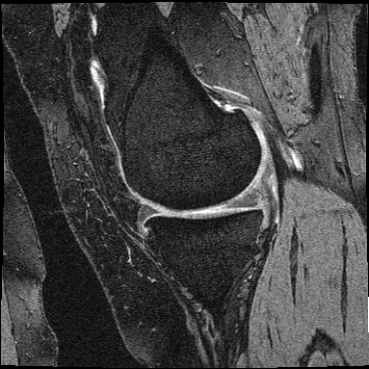

Inverse consistent rigid, affine, nonparametric, and MLP registration. We train networks on MNIST 5s using the methods in Secs. 3 and 4, demonstrating that the resulting networks are inverse-consistent. Our TwoStepConsistent (TSC) operator can be used on any combination of the networks defined in Sec. 3. For demonstrations, we join an MLP registration network to a vector field registration network, and join two affine networks to two vector field networks. Fig. 2 shows successful inverse-consistent sample registrations.

OAI Knee MRI We train and test on the split published with [22], with 2532 training examples and 301 test pairs from the Osteoarthritis Initiative (OAI) [16]444https://nda.nih.gov/oai. We evaluate using the mean Dice score of tibial and fibial cartilage. To compare directly to [22, 7, 23] we train and evaluate at [80x192x192].

| Moving Image | Warped Image | Fixed Image | Moving Image | Warped Image | Fixed Image |